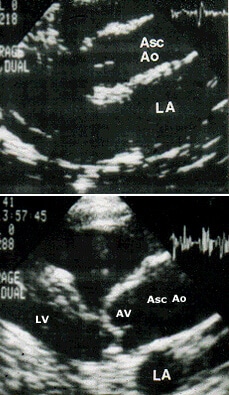

A imagem 2D da válvula aórtica normal, vista do eixo longo paraesternal, mostra dois folhetos (direito e não coronário), enquanto a vista do eixo curto paraesternal revela uma estrutura simétrica com três folhetos finos que se abrem igualmente, formando uma abertura circular durante a maior parte da sístole.

Realiza-se a ecocardiografia em modo M da valva aórtica juntamente com imagens 2D, direcionando o feixe em modo M através dos folhetos aórticos, conforme a vista transversal 2D.

As imagens em modo M de uma válvula aórtica normal apresentam algumas características:

- Na vista do eixo longo paraesternal, os folhetos aórticos abrem-se e fecham-se no ponto médio entre as paredes anterior e posterior da raiz aórtica;

- Após a abertura, os folhetos permanecem paralelos à raiz aórtica, quase tocando sua parede, até o final da sístole, criando uma forma de onda “em caixa” no modo M.

- Quando os folhetos estão em posição aberta durante a sístole, apresentam vibrações finas, que coincidem com um sopro sistólico inicial de baixa intensidade.

- Durante a diástole, os folhetos coaptados são movidos paralelamente à raiz aórtica.

Utiliza-se a ecocardiografia em modo M para avaliar o movimento da válvula aórtica, com variações nos padrões de movimento ajudando a diferenciar entre estenose aórtica grave e leve.

Nos casos de estenose aórtica, a ecocardiografia em modo M revela ecos densos e persistentes que substituem os padrões normais de movimento. Além disso, esses ecos podem não ser mais paralelos à aorta, o que indica a presença de estenose.